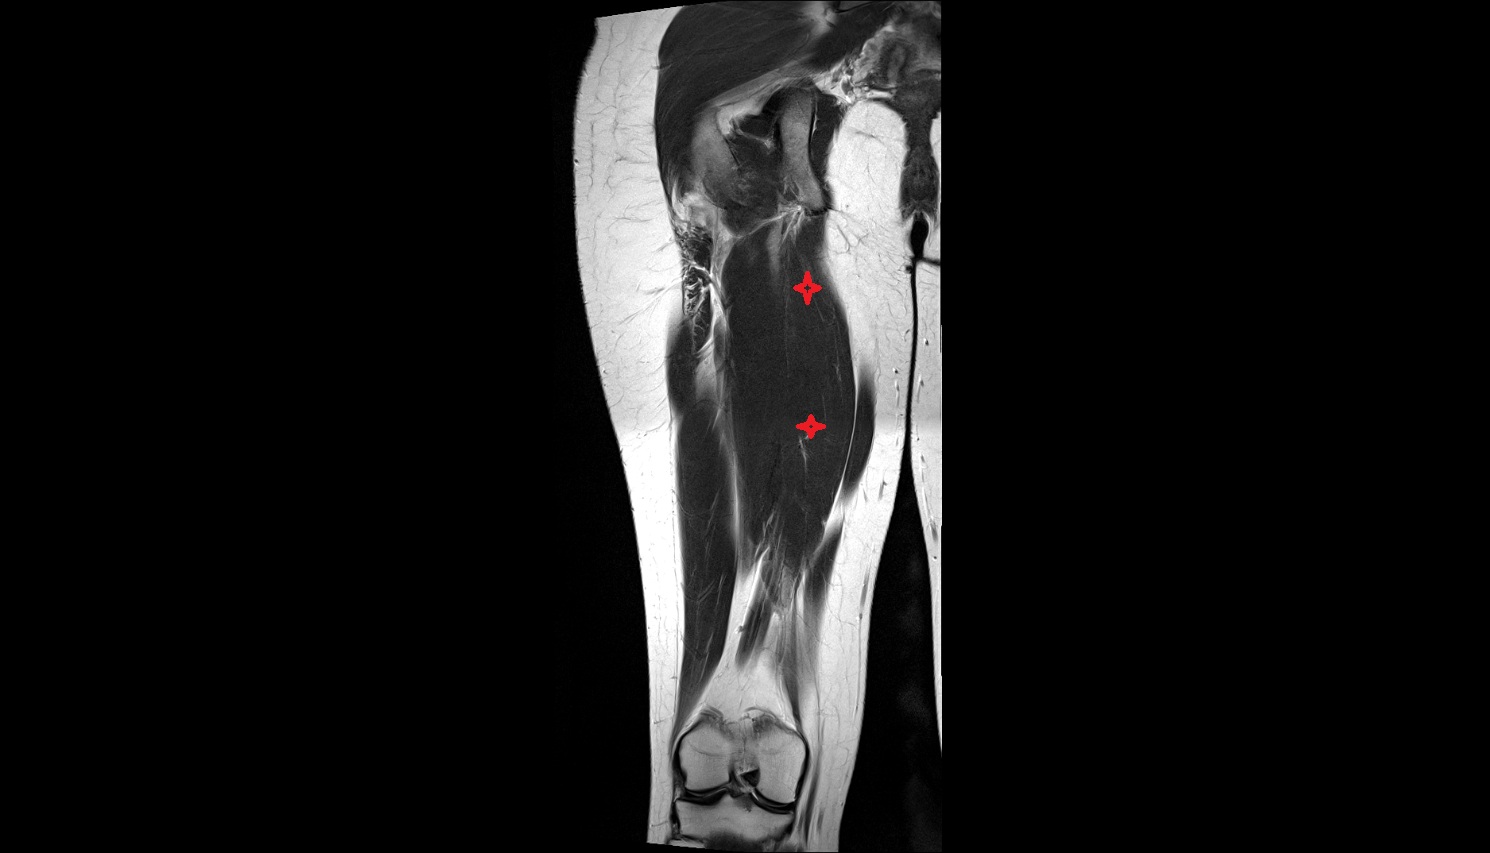

- Deep femoral artery (profunda femoris)

- Femoral artery

- Superficial femoral artery

- Deep femoral vein (profunda femoris vein)

- Biceps femoris muscle (Long head)

- Semitendinosus muscle

- Semimembranosus muscle